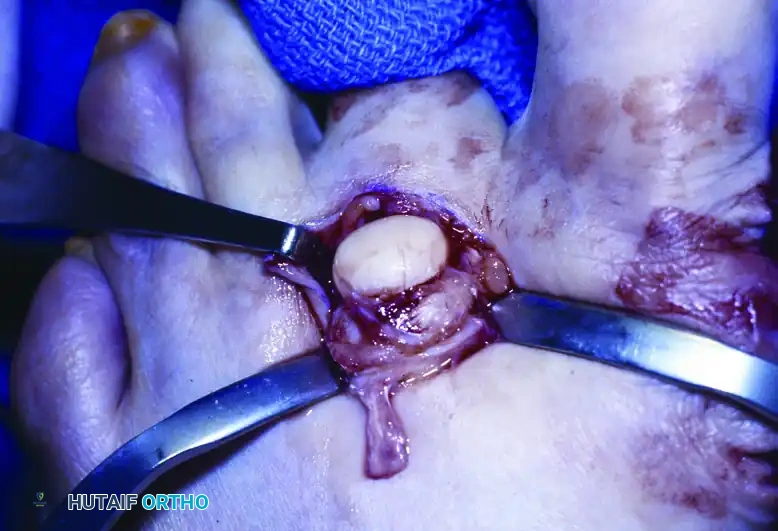

3. Bony Resection (Ostectomy)

The success of the procedure relies on the adequate removal of the underlying bony prominences.

* Deepen the dissection to expose the proximal phalanges of the involved toes. Protect the dorsal and plantar neurovascular bundles.

* Fourth Toe: Identify the base of the proximal phalanx. Using a microsaw or a sharp rongeur, resect the lateral flare of the base of the proximal phalanx of the fourth toe.

* Fifth Toe: Identify the head of the proximal phalanx. Resect the medial portion of the head of the proximal phalanx of the fifth toe.

* Smooth all resected bony edges with a rasp to ensure no sharp spicules remain that could cause recurrent internal pressure.

Do not resect the entire phalangeal head or base, as this will lead to profound instability of the digit. Only the prominent, offending condylar flares should be excised.